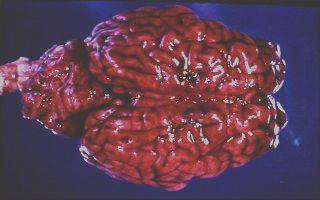

Nadoodse ondersoek

Bloed baie waterig, uriene donker, milt vergroot. Organismes kan in 'n bloedsmeer gesien word. In die geval van Europese rooiwater vertoon die brein dikwels donkerpienk van kleur soos hieronder gesien.